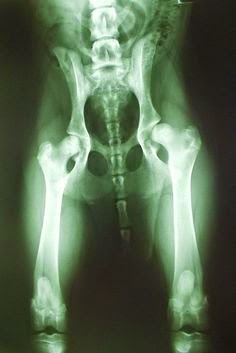

Köpeklerde kalça çıkığı nasıl bir rahatsızlıktır? Hal böyle olunca köpeklerde kalça çıkığı deformasyona uğrayarak hareket etmede kısıtlılık, topallama, zıplama hususunda isteksizlik, kemikte kireçlenme ve bununla birlikte ağrı hissi meydana gelir. Kalça çıkığı olan köpekler genellikle göze çarpan kellikten muzdariptir. Belirtiler bir yaşın altındaki yavru köpeklerde kalça çıkığı, topallama.

Kalça çıkığı, (baytar kişileri buna havalı olsun diye displazi derler.) kalça eklemindeki uyumsuzluk ve buna bağlı olarak şekillenen gevşeklik nedeniyle. Köpeklerde kalça çıkığı displazisi belirtiler tedavisi. Sonuçta, köpeklerde kalça çıkığı kalça ekleminde bozukluğa neden olur. Bu makaleden alıntı yapmak için alıntı yapılan yazıya aşağıdaki ibare eklenmelidir: